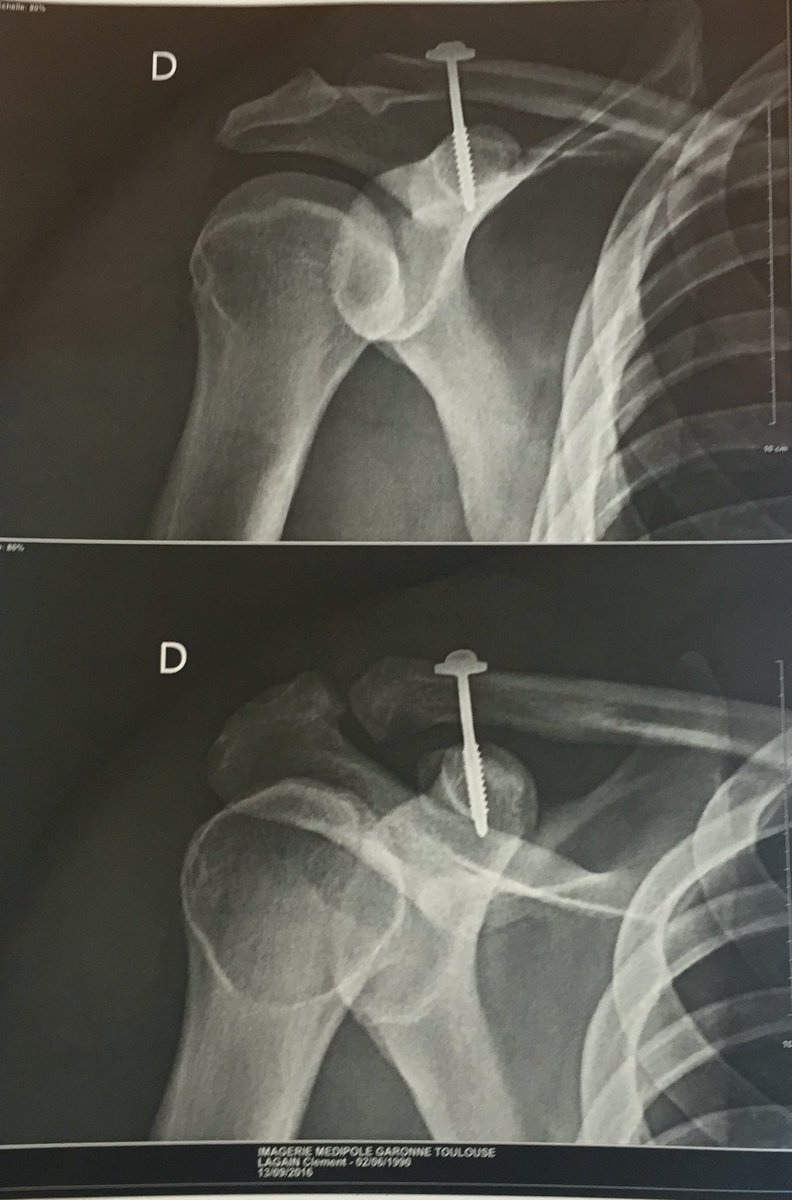

Rupture du ligament coraco-claviculaires, opération prévu lundi matin! 4 mois sans fouler le pré🤕😰 #colomiers #epauleencarton